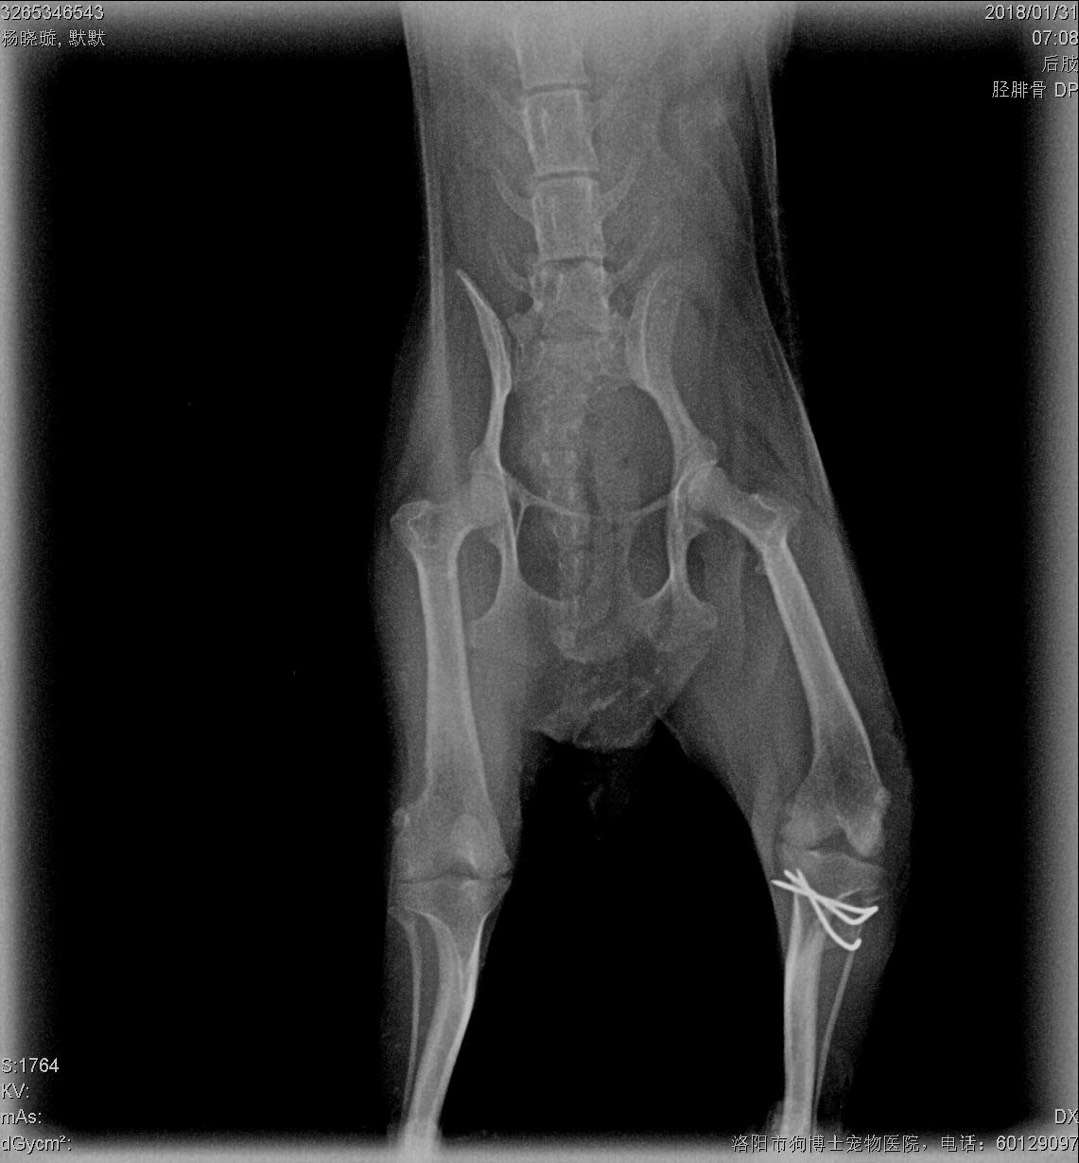

微茶髕骨移位手術一例:微茶妹妹,雙側(cè)髕骨3級移位移位,同時實施滑車溝再造術、脛骨粗隆移位術、及髕骨周圍軟組織修復術。手術期間,呼吸麻醉,心電監(jiān)護,手術持續(xù)2小時,一切順利,住院護理中。